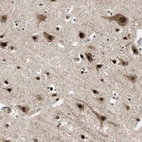

Immunohistochemical staining of human brain shows strong nuclear and cytoplasmic positivity in neurons.